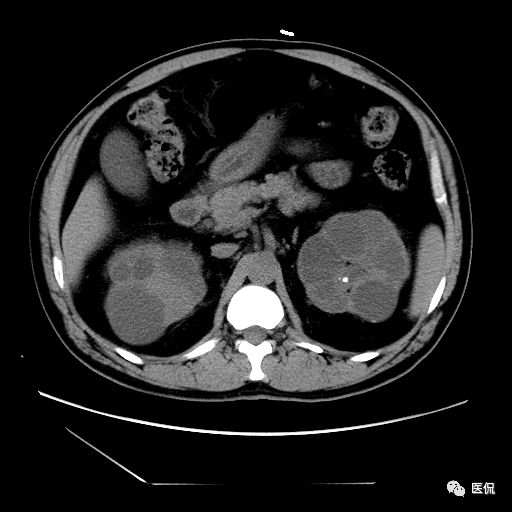

双肾实质可见多发囊性密度灶,其内密度不均匀,并可见钙化灶,增强扫描未见明显强化灶。肾周脂肪间隙清晰,与邻近组织分界清楚。

多囊肾的 CT 表现主要表现为双肾增大,轮廓光滑或有分叶,肾实质内多个大小不等的囊肿呈蜂窝状,多呈水样低密度,增强扫描囊肿本身无强化,而囊肿间正常肾组织增强,对比明显。当囊肿张力过高,使囊壁上毛细血管牵拉破裂出血时,表现为囊肿内稍高密度影,随访CT 值减低。囊壁钙化,表现为点线状高密度影像,随访CT值无变化。有文献报道约 30%病例可并发多囊肝或多囊胰。